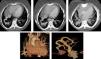

El drenaje del pulmón derecho se realizaba mediante VVPP de trayecto anómalo, desembocando en un vaso que comunicaba con la aurícula izquierda (AI) en un extremo y la vena cava inferior (VCI) en otro. No existían otras malformaciones asociadas. Los hallazgos fueron compatibles con un síndrome venolobar congénito (fig. 1).

En el panel superior se ve una secuencia de cortes axiales de TAC con la doble conexión del vaso aberrante a AI y VCI. En el panel inferior a la izquierda se observa una reconstrucción tridimensional del corazón y grandes vasos con la vena aberrante, y en el panel inferior a la derecha se muestra una reconstrucción de la vena aberrante con sus dos extremos a VCI y a AI.